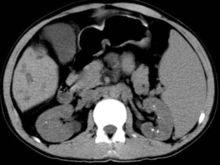

影像診斷

Caroli病 CT腹部平片肝內多個散在大小不等囊狀低密度影,CT值近似水,病灶與膽管相通,中央見稍高密度點狀影,以肝右葉病灶明顯,近端膽管及肝外膽管無擴張。肝裂增寬;脾臟明顯腫大,下極位於第1骶椎平面;門脈、脾血管明顯迂曲、擴張。雙側腎臟實質內見多發模糊低密度影,腎盂及腎盞內見多枚大小不等點狀高密度影。增強掃描,肝內囊狀病灶無明顯強化,其內點狀稍高密度影強化程度高於正常肝實質;雙側腎臟實質內低密度影無強化,境界顯示較平掃清晰。門脈及脾血管強化明顯。後腹膜區未見腫大淋巴結,腹腔無積液以肝內多個散在大小不等囊狀低密度影,CT值近似水,病灶與膽管相通,中央見稍高密度點狀影,以肝右葉病灶明顯,近端膽管及肝外膽管無擴張。肝裂增寬;脾臟明顯腫大,下極位於第1骶椎平面;門脈、脾血管明顯迂曲、擴張。雙側腎臟實質內見多發模糊低密度影,腎盂及腎盞內見多枚大小不等點狀高密度影。增強掃描,肝內囊狀病灶無明顯強化,其內點狀稍高密度影強化程度高於正常肝實質;雙側腎臟實質內低密度影無強化,境界顯示較平掃清晰。門脈及脾血管強化明顯。後腹膜區未見腫大淋巴結,腹腔無積液(以上內容為貴陽醫學院肝膽外科10級研究生王政 歸納整理)。